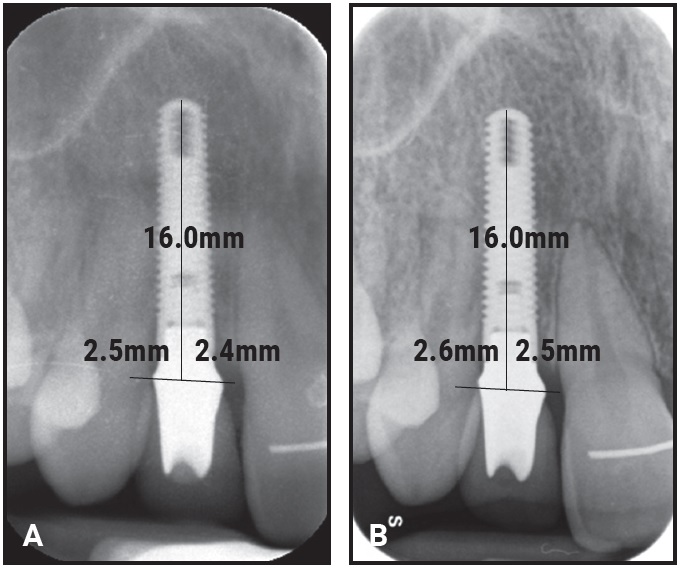

In the IMP group, periapical radiographs were taken with the parallel technique at final crown delivery (baseline, T1) and at follow-up (T2) for evaluation of the crestal bone levels around the implants (Fig. 4). To calculate the change from T1 to T2, the distances from the crown-abutment junction to the first visible mesial and distal bone-to-implant contacts were measured at each time point.45,46 The radiographs were calibrated by adjusting them to the actual length of the various implants using the Dolphin Imaging 11.9 Annotations** program. Calibrated frontal intraoral photographs in maximum intercuspation, centered at the upper dental midline and parallel and slightly superior to the occlusal plane, were used to assess the development of visible infraocclusion between T1 and T2 (Fig. 5). All photographs were taken with a Canon EOS 700D*** digital camera using an EF 100mm f/2.8 Macro USM lens and Macro Ring Lite MR-14 EXII flash.

Fig. 4 Example of periapical radiographs used to measure distances from crown-abutment junction to first visible mesial and distal bone-to-implant contacts at baseline (A) and follow-up (B).

No statistically significant difference in clinical periodontal condition could be observed between the two patient groups. Comparison of the IMP periapical radiographs at T1 and T2 revealed only minor changes between the marginal bone levels at baseline (crown delivery) and follow-up. The mean differences in implant-to-bone distance from T1 to T2 were .32mm on the mesial and .34mm on the distal sides of the implants (Table 3). Differences between baseline and follow-up were statistically significant (p < .001), but there was no significant difference between the mesial and distal sides of the implants (p = .868).